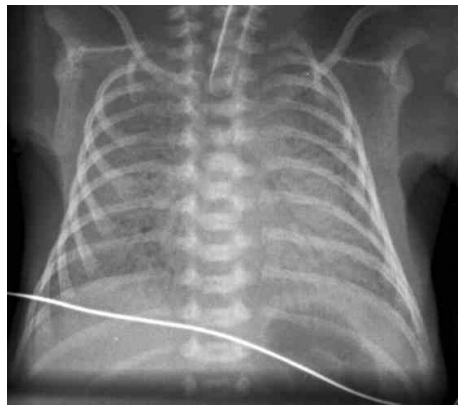

6 一位於母親懷孕 28 週時出生的新生兒,出生後有明顯呼吸窘迫現象,胸部 X 光如圖所呈現,此嬰兒 最適當的治療是: (A)一氧化氮吸入性治療(nitric oxide inhalation) (B)表面張力素(surfactant) (C)廣效抗生素(broad spectrum antibiotics) (D)類固醇(steroids)

7 一個足月兒出生體重 4.8 公斤,以頭位自產道產出,出生後之身體診察發現此嬰兒之驚嚇反射(Moro reflex)不對稱,右側沒有反應。此嬰兒同時有發紺現象伴隨不規則的費力呼吸,呼吸時兩側胸部動 作不對稱,右側肋緣下沒有明顯凹陷,聽診時右側肺部呼吸音較小聲;此新生兒的臨床診斷最可能 是下列何者? (A)右側氣胸 (B)左側肺部塌陷 (C)右側上臂神經叢傷害 (D)右側下臂神經叢傷害